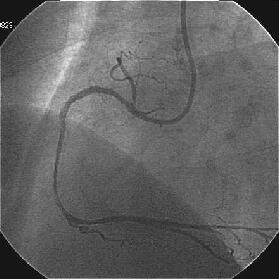

Crush�̎�Z�B

|

|

|

|